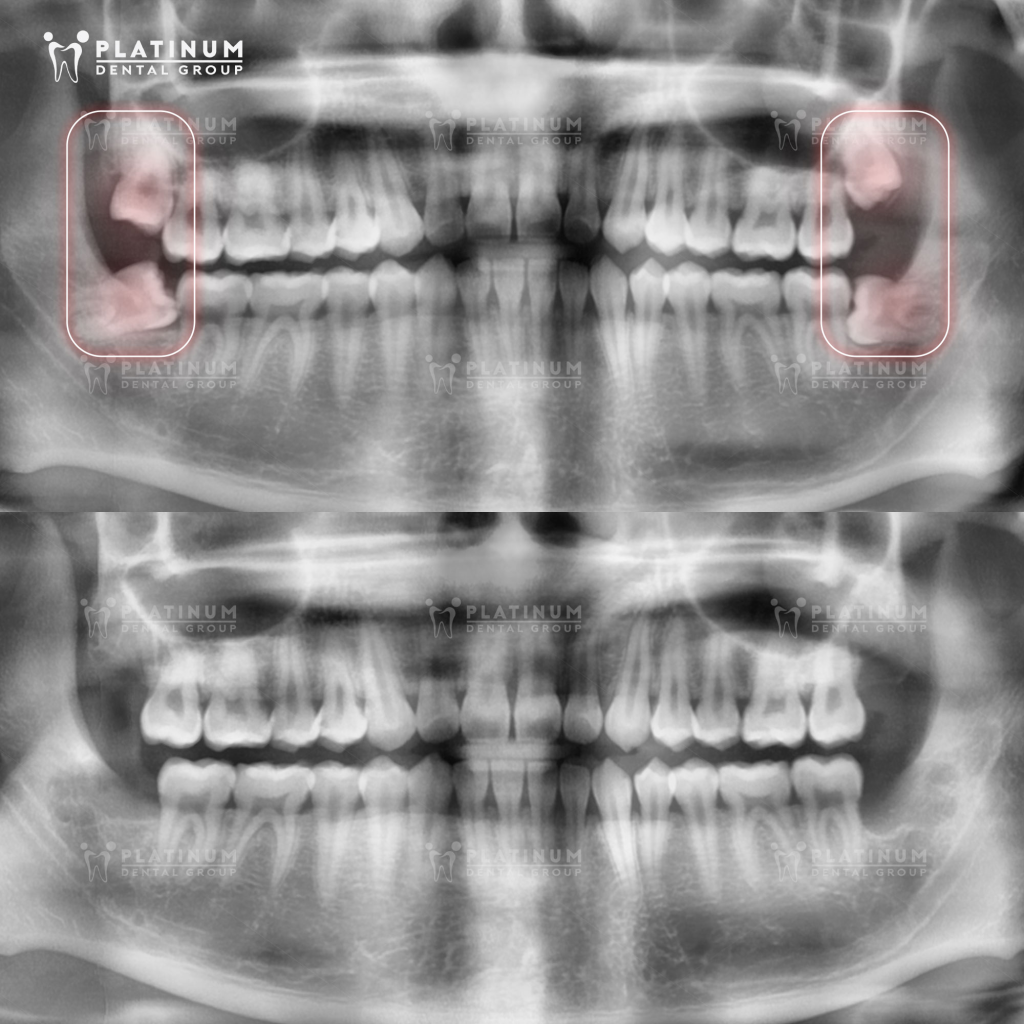

Chụp CT ConeBeam 3D xác định vị trí răng

Trước khi nhổ răng số 8, người bệnh thường được chỉ định chụp CT ConeBeam 3D. Hình ảnh 3 chiều cho phép bác sĩ quan sát rõ:

- Hướng mọc và mức độ mọc ngầm của răng

- Hình dạng và số lượng chân răng

- Khoảng cách giữa chân răng và dây thần kinh hàm dưới hoặc xoang hàm trên.

Nhờ đó, bác sĩ có thể tiên lượng mức độ khó của ca nhổ, lựa chọn kỹ thuật phù hợp và hạn chế tối đa nguy cơ tổn thương các cấu trúc giải phẫu quan trọng.

- Kết quả chụp phim cho thấy hướng mọc bất lợi: Ngay cả khi chưa có triệu chứng rõ ràng, nếu phim X-quang hoặc CT 3D cho thấy răng số 8 mọc lệch, mọc ngang, mọc ngầm sâu hoặc có nguy cơ gây biến chứng trong tương lai, bác sĩ có thể khuyến nghị nhổ sớm. Can thiệp ở giai đoạn này thường nhẹ nhàng hơn và thời gian hồi phục nhanh hơn.